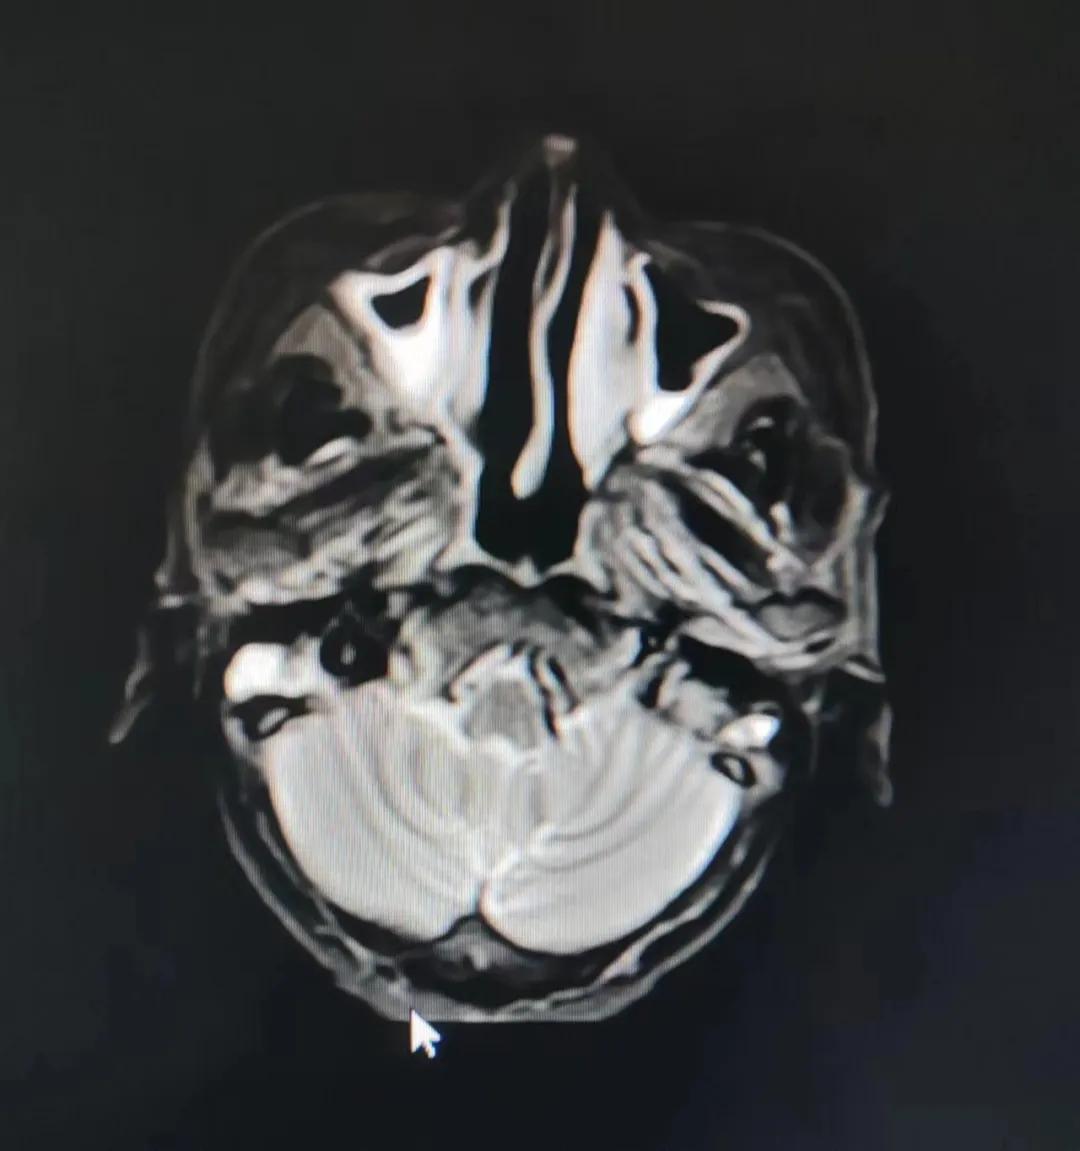

治療前

老人因鼻部腫物堵塞鼻腔并且侵犯鼻咽導致鼻塞、疼痛、吞咽困難,身心都備受煎熬,趙亮主任在詢問其病史期間幾度落淚。趙亮主任向患者及家屬解釋說:“現代放療比過去的傳統放療設備先進,技術不斷提升,能對腫瘤區域的照射劑量進行優化,做到準確定位、精準照射,同時,最大限度地降低正常組織的受量,對全身情況影響很小。”

考慮到患者年齡較大、體質差,手術難度大,且常規的放射治療難以保護患者晶體造成患者雙眼視力損傷,放療團隊以最快的速度制定了精準放射治療方案并開始為其實施治療。僅僅數日后,老人腫塊出血即得到控制,腫塊明顯縮小,放療20次后腫塊迅速縮小!